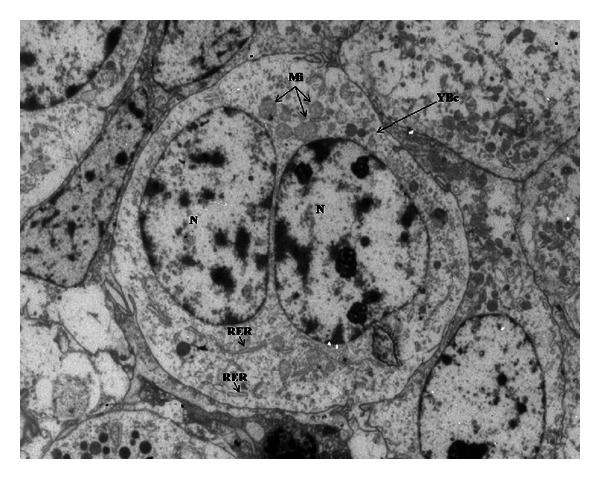

The aim of this study was to evaluate the effect of feed restriction followed by a realimentation with monensin supplementation on morphological, ultrastructural, and apoptotic characteristics in the term placenta of Anglo-Nubian does. Treatments were a control group (C = 5), a group fed at 0.70 of that consumed by controls (R = 7), and the same as R with monensin (M = 7). After parturition, 27 placentas were gathered, C: 7, M: 10, and R: 10. No differences were detected between treatments in relation to morphological and ultrastructural analysis. The greatest values of binucleate cells were detected in placentas from R, and it could be due to the need to compensate and satisfy nutritional differences of restriction. We detected the highest apoptotic index in R as a consequence of nutritional treatment. We describe for the first time the structural and ultrastructural morphology and remodeling by apoptosis of Anglo-Nubian placenta at term of goats subjected to nutritional restriction during peripubertal period and the use of monensin as a growth promoter.

本研究的目的是评估限饲后补充莫能菌素再饲喂对英努比山羊足月胎盘的形态、超微结构和凋亡特征的影响。处理组包括对照组(C = 5只)、按对照组采食量的0.70饲喂的组(R = 7只),以及与R组相同但添加莫能菌素的组(M = 7只)。分娩后,收集了27个胎盘,C组7个,M组10个,R组10个。在形态和超微结构分析方面,各处理组之间未检测到差异。在R组的胎盘样本中检测到双核细胞的最高值,这可能是由于需要补偿和满足限饲造成的营养差异。由于营养处理,我们在R组中检测到最高的凋亡指数。我们首次描述了在青春期前后受到营养限制的山羊足月时英努比胎盘的结构和超微结构形态以及凋亡重塑情况,以及使用莫能菌素作为生长促进剂的情况。